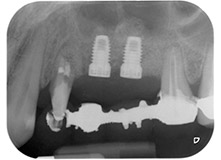

Поставяне на имплант 26 на ниски обороти

Фиг. 11: Поставяне на имплант 26 на ниски обороти с ограничение на въртящия момент 35 Ncm.

готовност за покривни винтове

Фиг. 12: Двата импланта са на място и са готови за поставяне на покривни винтове.

Накрая, след периостален разрез, мястото е пасивно зашито с коронарно напреднало ламбо, използвайки 5-0 абсорбиращ конец (Фиг. 15). Следоперативната рентгенова снимка показва, че и двата импланта са в правилна вертикална позиция (Фиг. 16).

Следоперативна рентгенова снимка

Фиг. 16: Следоперативната рентгенова снимка показва, че имплантите са на място и костозаместващия материал от вътрешния синус лифт около апекса. Има малко видим материал от GTR процедурата около каналите на зъб 24.